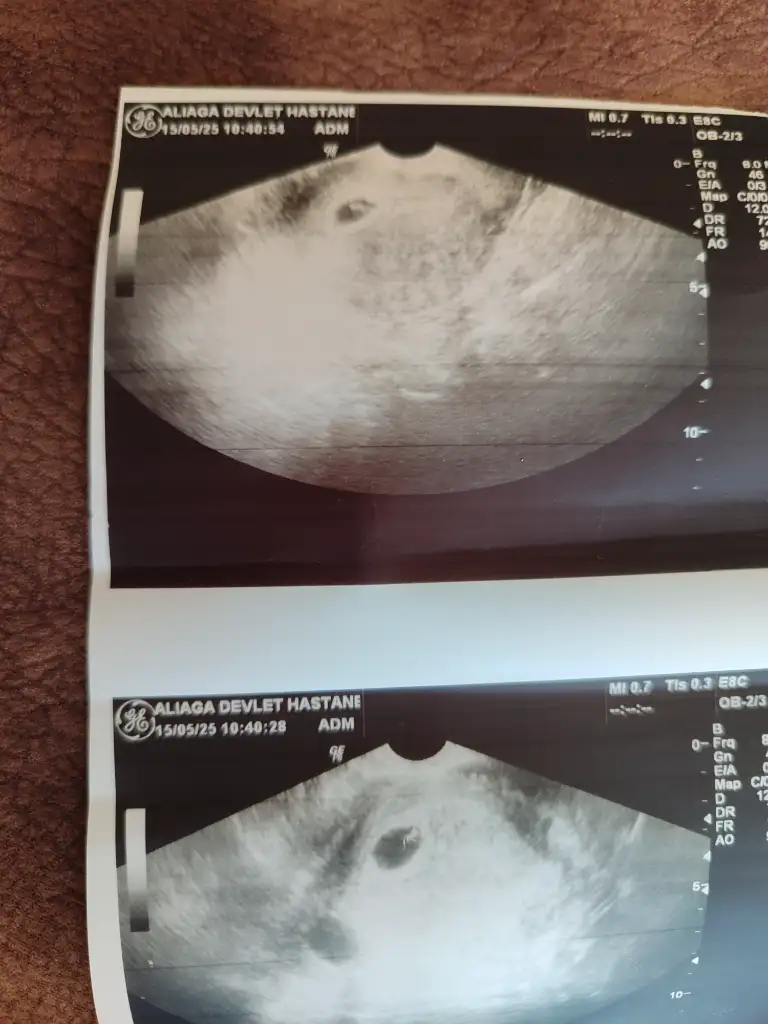

Benim de vajinal bakıldı ultrason yorum yapar mısınız sizce nedirKarindan mi vajinal mi peki

Ramziye göre kız ama daha çok erken tabi sağlıkla gelsinBenim de vajinal bakıldı ultrason yorum yapar mısınız sizce nedir

Benim de vajinal bakıldı ultrason yorum yapar mısınız sizce nedir

Yaaa banada bakarmisiniz rica etsem vajinal bakıldı bugünGerçi vajinal dediniz dimi çok özür dilerim kese sağda valla hamilelik bende dalgınlık yapıyorevet kese yerine göre erkek

Aynı canım kese sağda ramzi teorisine göre erkek sağlıkla gelsinYaaa banada bakarmisiniz rica etsem vajinal bakıldı bugün